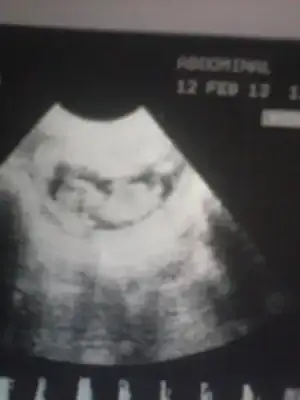

heycanım gitgide üst düzeye çıktı..kalbim sürekli çarpıyor.bebeğim 16 hafta 5 günlük oldu.yarın dr.a gidicem ama inanın gitmek istemiyorum.çok korkuyorum.ya bebeğime birşey olursa.ya omurgası açıksa diye.ben ilk bebeğim kaybettim.omurga açıklığından.2.ye sağlıklı bir kızım oldu.ama korkularım hiç geçmedi.bu 3.bebeğim olucak rabbim izin verirse inşallah.yarın güzel haberlerle dönmek çok istiyorum.ve hemen size buradan yazıcam.benim içinde dua edin neolur buna ihtıyacım var.hayırlısıyla bebeğimin sağlığı yerinde olsun......cinsiyet merakım ise yok oldu gitti.

canım benim için erkek dediysen neresine baktında anladın ben baktım baktım bişey anlamadım.gerçi dr.da erkeğe benziyor dedi.ama içimden bir kız geçiyor hayırlısı.yarın rabbimin izniyle herşey belli olucak ama benim başka korkularım var omurga açıklığı korkusu inşallah bebeğim sağlıklıdır.

Telden giriyorum resmi iyice yaklaştırıyoruz baktım çıkıntı yukarda korkuların yarın sona erer umarım çok stres yapma ama